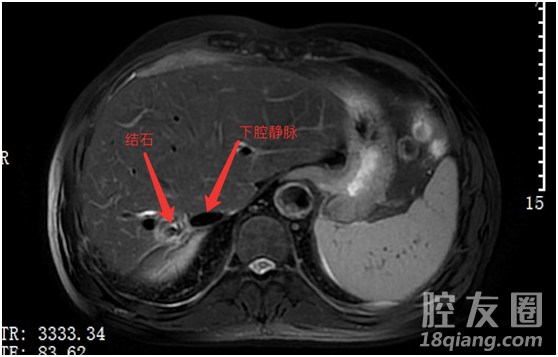

考虑到楼大爷的年纪比较大,以及做过两次开放性手术,萎缩的右肝与肝后下腔静脉紧密粘连,解剖结构不清晰,术中极易引起大出血,因此,手术风险非常高。

磁共振图像

10月28日,经过充分的术前准备,楼大爷被送入手术室,进行:肝内鞘外解剖右半肝切除术。术中确实如术前判断的一样:发现患者右肝严重萎缩,与肝后下腔静脉致密粘连。